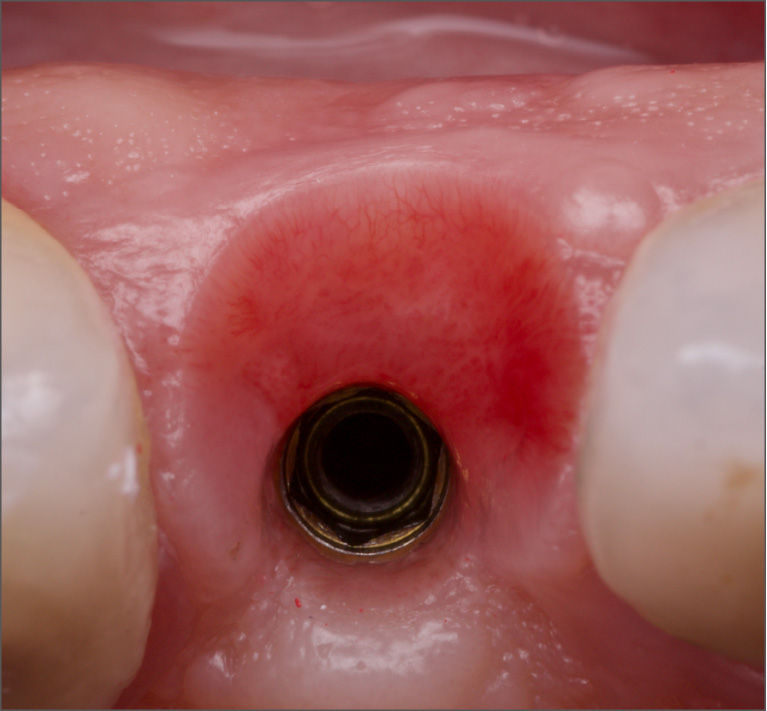

La morfologia convergente del collo Prama permette di recuperare la porzione di tessuto molle che con un impianto transmucoso tradizionale verrebbe occupata dal titanio del collo implantare. La convergenza di Prama fa sì che i volumi intorno alla porzione coronale dell’impianto vengano invece riempiti di coagulo e di importanti fattori di ricrescita, che si trasformano in tessuti molli spessi e funzionali.

L'ispessimento della gengiva che circonda il collo Prama rappresenta un beneficio indiscusso, soprattutto nei pazienti con biotipo più sottile, nei quali questo innovativo impianto apporta un ispessimento dei tessuti molli senza ricorrere a terapie rigenerative.

La stabilizzazione del connettivo, resa possibile dalla morfologia convergente e dalla microrigatura UTM, fa sì che tutto ciò che vi è al di sotto rimanga protetto e isolato da potenziali attacchi batterici, e che quindi l’osso si mantenga preservato in maniera efficace e a lungo, come ampiamente dimostrato dalla clinica.